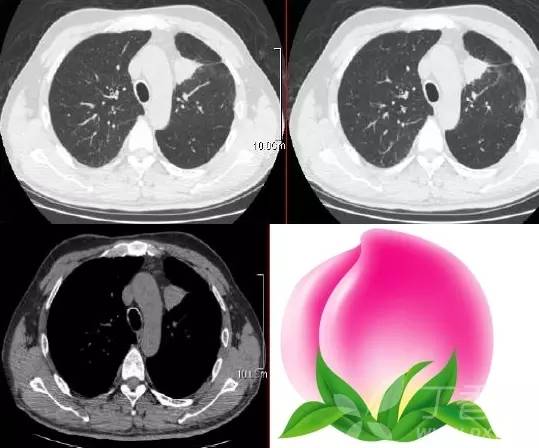

桃尖征是指肿块某一边缘尖角状突起形似桃尖,是炎性假瘤包膜的粘连牵拉,为良性肿块尤其是炎性假瘤特有。

由于肿瘤大多位于肺的浅表部位,邻近胸膜常出现炎性反应,继之局限性的胸膜增厚、粘连,于肿物边缘可见类似胸膜幕状粘连的尖角状表现,这种尖角和肿块连在一起酷似一个桃子的桃尖。